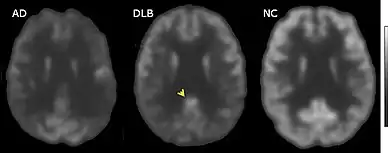

Direct laboratory-measurable biomarkers for DLB diagnosis are not known, but several indirect methods can lend further evidence for diagnosis.[25] The indicative diagnostic biomarkers are: reduced dopamine transporter uptake in the basal ganglia shown on PET or SPECT imaging; low uptake of 123iodine-metaiodobenzylguanidine (123I-MIBG) shown on myocardial scintigraphy; and loss of atonia during REM sleep evidenced on polysomnography. Supportive diagnostic biomarkers (from PET, SPECT, CT, or MRI brain imaging studies or EEG monitoring[124]) are: lack of damage to medial temporal lobe (damage is more likely in AD[116]); reduced occipital activity; and prominent slow-wave activity on EEG.[25]

If DLB is suspected when parkinsonism and dementia are the only presenting features, PET or SPECT imaging may show reduced dopamine transporter activity. A DLB diagnosis may be warranted if other conditions with reduced dopamine transporter uptake can be ruled out.[25]

The symptoms of DLB are easily confused with delirium,[139] or more rarely with psychosis;[114] prodromal subtypes of delirium-onset DLB and psychiatric-onset DLB have been proposed.[21] Mismanagement of delirium is a particular concern because of the risks to people with DLB associated with antipsychotics.[139] A careful examination for features of DLB is warranted in individuals with unexplained delirium.[140] PET or SPECT imaging showing reduced dopamine transporter uptake can help distinguish DLB from delirium.[139]

PET or SPECT imaging can be used to detect reduced dopamine transporter uptake and distinguish AD from DLB.[57][149] Severe atrophy of the hippocampus is more typical of AD than DLB.[150] Before dementia develops (during the mild cognitive impairment phase), MRI scans show normal hippocampal volume. After dementia develops, MRI shows more atrophy among individuals with AD, and a slower reduction in volume over time among people with DLB than those with AD.[33] Compared to people with AD, FDG-PET brain scans in people with DLB often show a cingulate island sign.[33]